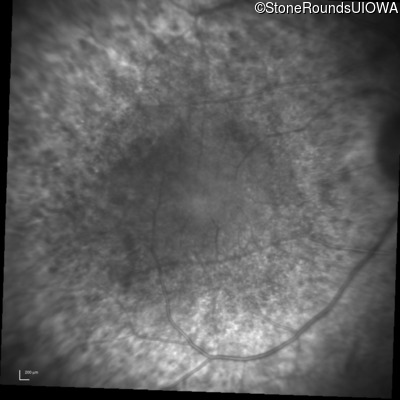

Infrared Fundus Photograph - Right - 20/25

Exemplar